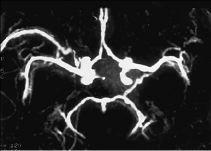

Angiografía con tomografía axial computarizada espiral (helicoidal)

Nuevamente los avances tecnológicos en el diagnóstico por imagen han revolucionado la práctica y el concepto de la angiografía cerebral. La TACE ofrece una nueva forma de evaluar la anatomía vascular intracraneal después de la inyección por vía intravenosa de contraste en forma de embolada rápida con un inyector automático. La adquisición de las imágenes se realiza en dos fases consecutivas; la primera fase da comienzo a los 20 segundos después de la introducción del contraste a una velocidad de 3 ml/seg con una velocidad de desplazamiento del paciente de 10 mm y una colimación de 10 mm (pitch 1:1) y la segunda con los mismos parámetros y repitiendo igualmente el mismo recorrido anatómico craneal, de tal modo que se comienza a los 54-60 segundos desde el comienzo de la inyección del medio de contraste. Las imágenes axiales se reconstruyen cada 5 mm, pudiendo realizar posteriores reconstrucciones tridimensionales o con técnica de máxima intensidad de proyección MIP (fig. 7).

Fig. 7. Angiografía con tomografía computarizada espiral craneal con contraste normal con reconstrucción del polígono de Willis en una imagen reconstruida con técnica MIP en proyección axial y visto desde el extremo craneal del paciente.

La TACE es un método relativamente poco invasivo, muy rápido y eficaz, constituyendo una interesante alternativa a la angiografía cerebral convencional y digital para la valoración del flujo arterial y venoso intracraneal8.

Catorce pacientes en muerte encefálica fueron estudiados con TACE por Dupas et al8 y este grupo fue comparado con once sujetos sanos que actuaron de controles. Asimismo, se hizo EEG en siete ACIA en cinco y ambas en dos, con una especificidad de la angiografía del 100%. En estos casos de muerte encefálica encontraron una ausencia de contraste en basilar, pericallosas, arterias corticales y venas profundas y senos sagital superior y recto.